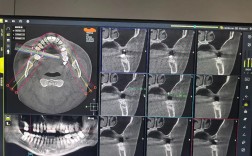

种植牙对上颌骨厚度有非常直接且重要的影响,可以说上颌骨的厚度(以及高度)是决定种植牙成功与否和手术方案的关键因素之一,以下是种植牙与上颌骨厚度关系的详细说明:上颌骨厚度的重要性种植体植入的基础:种植体需要植入到牙槽骨(上颌骨的一部分)中,...